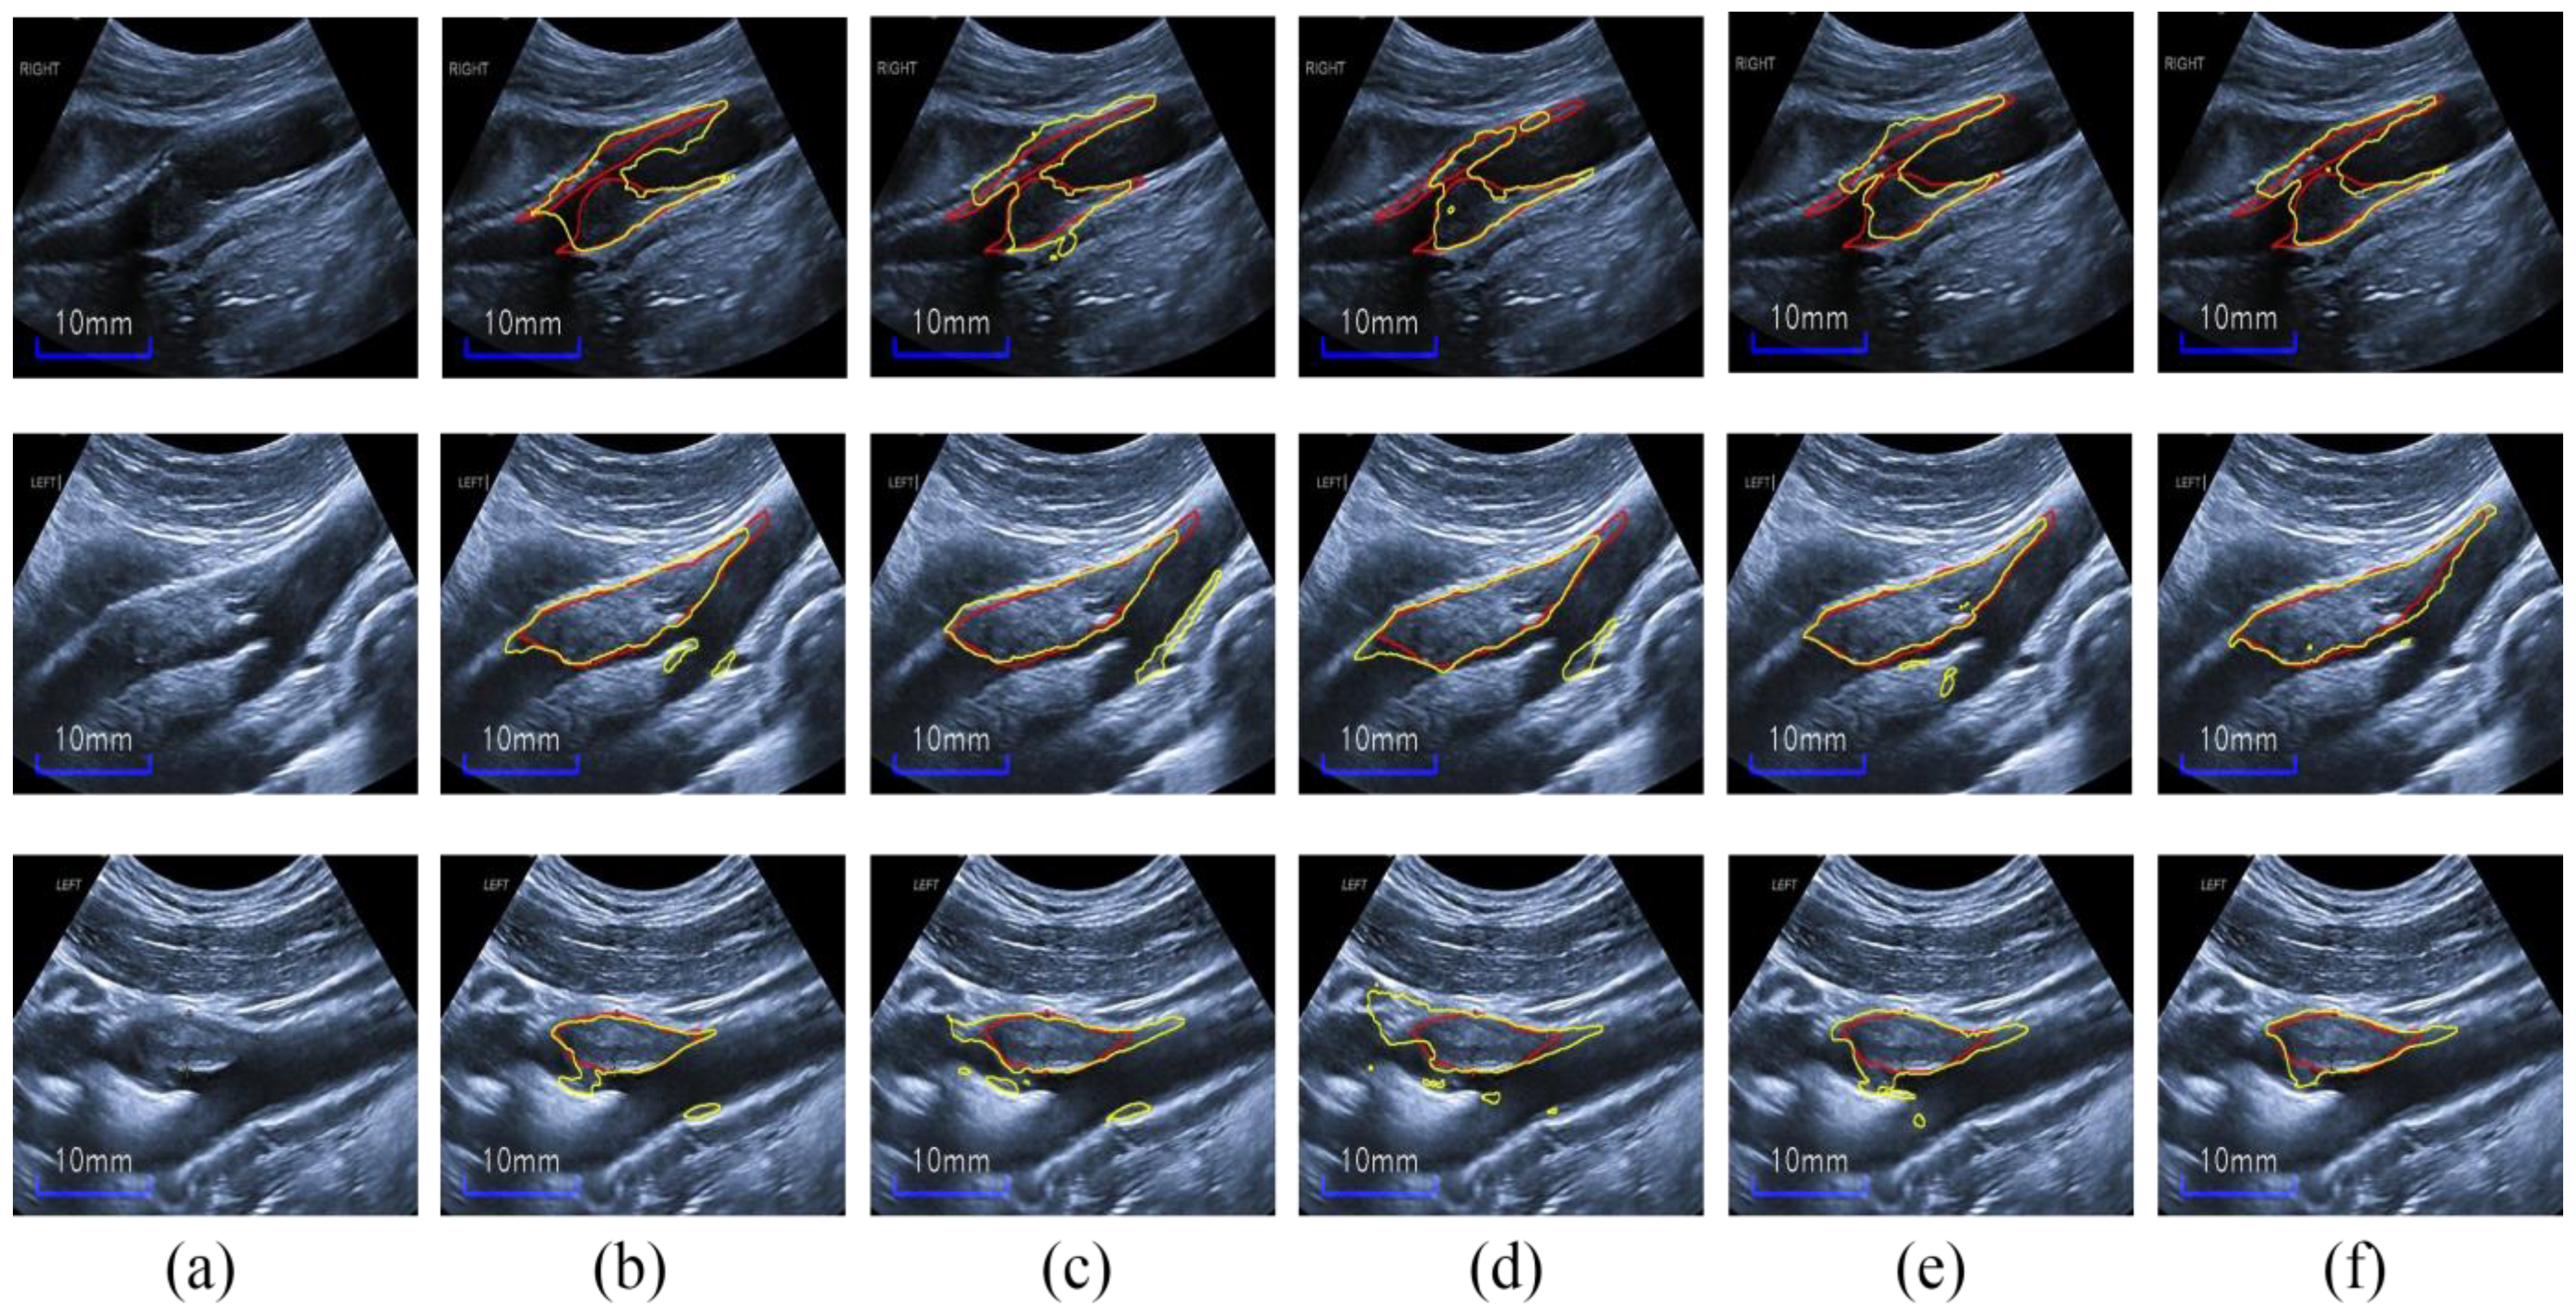

4.1. Compared with State-of-the-Art Methods

4.2. Ablation Study

4.2.1. Effect of Each Module